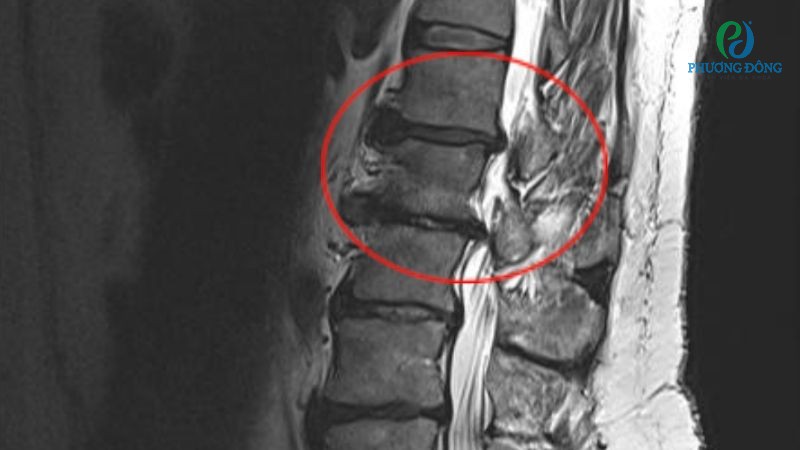

- Chụp CT hoặc MRI nhằm quan sát chi tiết hơn cấu trúc cột sống, xem xét tình trạng tổn thương thần kinh cùng các bệnh lý khác.